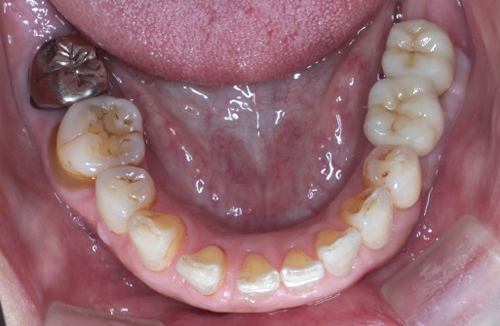

【お悩み】

奥歯を失ってから、食事の際にしっかり噛めず不便を感じていました。入れ歯には抵抗があり、インプラントを検討して来院されました。

【診断】

歯科用CT検査により、インプラントに必要な骨量が十分にあることを確認しました。

【治療内容】

骨造成は行わず、患者さまの状態に合わせたインプラント治療を行いました。

【治療後】

治療後は奥歯でしっかり噛めるようになり、食事のストレスがなくなったとお話しされています。

【この症例のポイント】

一般的な奥歯の欠損であれば、状態によっては比較的シンプルな治療計画でインプラントが可能なケースもあります。